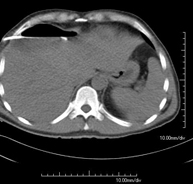

Prova diagnòstica que consisteix en l'estudi de l'abdomen d'alta definició anatòmica (fetge, vesícula biliar, via biliar, pàncrees, melsa, estómac, intestins, ronyons, estructures vasculars, bufeta, úter i ovaris, etc.) mitjançant l'ús d'un equip de TC (Tomografia Computeritzada). Aquestes imatges s'estudien posteriorment en una estació de treball que permet obtenir reconstruccions bidimensionals en diferents plànols de l'espai i també reconstruccions 3D (volumètriques). La majoria d'estudis requereixen l'ús de contrast iodat per millorar la definició de les imatges. - TC Pelvis

Prova diagnòstica que consisteix en obtenir imatges bi i tridimensionals de l'abdomen d'alta definició anatòmica (estructures òssies, estructures vasculars, fetge, pàncrees, vesícula biliar, ronyons, glàndules suprarenals, melsa, intestí prim i gros, bufeta, úter i ovaris, pròstata i vesícules seminals, urèters, etc.) mitjançant l'ús d'un equip de TC (Tomografia Computeritzada). La majoria d'estudis requereixen l'ús de contrast iodat. - TC Fetge